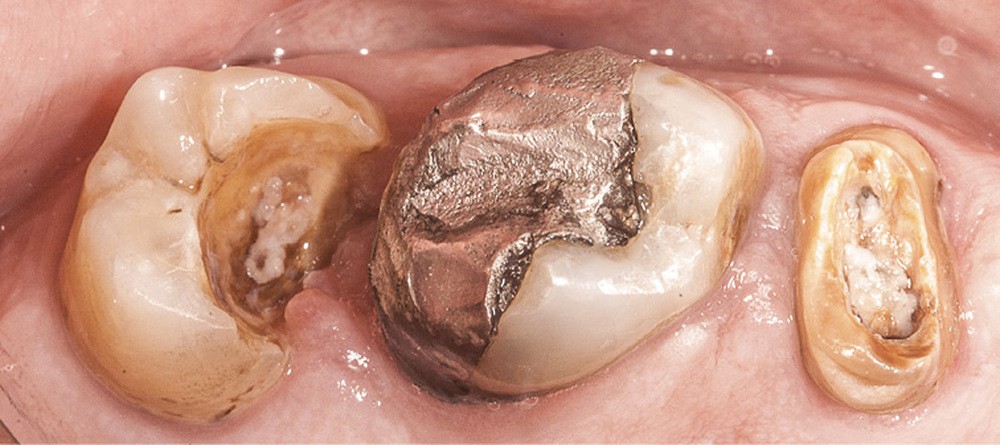

En dentisterie restauratrice, la tendance actuelle est, dans la mesure du possible, de « copier la dent naturelle grâce aux restaurations adhésives en céramique » [1]. Cependant, les tissus dentaires sont soumis à différents « outrages » qui peuvent être à l’origine de pertes de substance parfois très importantes. Contrairement à ce que l’on peut penser, et ce malgré les progrès indéniables rendus possibles par la prévention dans cette spécialité, le praticien se trouve encore trop souvent confronté à des pertes de substance majeures, voire irrémédiables (fig. 1). L’évaluation précise de la qualité des tissus résiduels constitue une étape essentielle permettant au praticien de proposer une thérapeutique adaptée au patient [2].